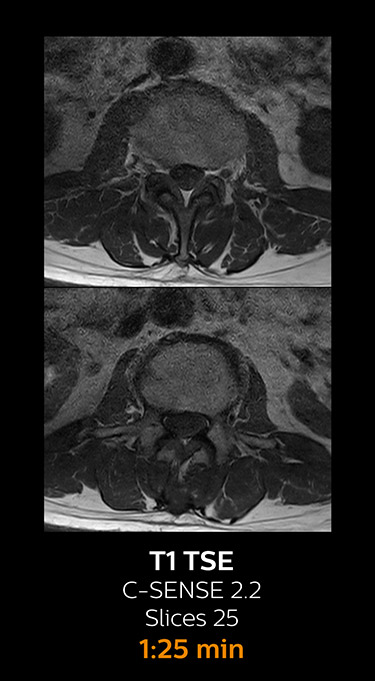

Fast MRI of lumbar spine

which corresponds to 34% reduction.

With Compressed SENSE, the scan time for the routine lumbar spine examination at KNC was reduced from 11:41 to 8:17 minutes,

MRI examination of the lumbar spine with Compressed SENSE

Ingenia 3.0T CX

Scan time 8:17 min. (was 11:41 min. without Compressed SENSE)